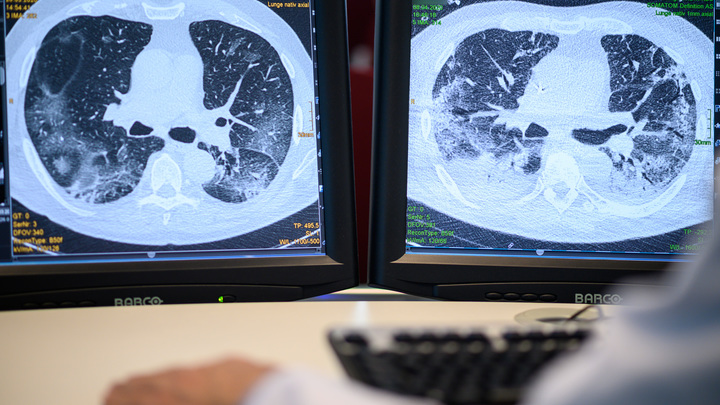

Вскрытие показало: Учёные нашли ответ на важный вопрос о COVID-19

Учёные нашли ответ на важный вопрос о последствиях COVID-19. Вскрытие показало, в чём причина одного из самых распространённых последствий.

Американский исследователь, доктор медицинских наук Стивен Ментцер совместно с учёными из других стран выявил причину большинства летальных исходов заражения коронавирусом.

Вскрытие тел умерших от COVID-19 показало, что в образцах лёгочной ткани некоторых скончавшихся от коронавируса людей были обнаружены признаки прогрессирования лёгочных сосудистых заболеваний. Именно это объясняет нарушение свёртываемости крови у пациентов.

"Повреждённые вирусом кровеносные сосуды также могут лежать в основе других проблем, которые наблюдаются у заболевших COVID-19", - сообщают исследователи.

Отмечается, что это "осложнения в виде синдрома Кавасаки у детей, инсультов и прочих проблем, которые, казалось бы, не связаны с вирусом", отметили исследователи.